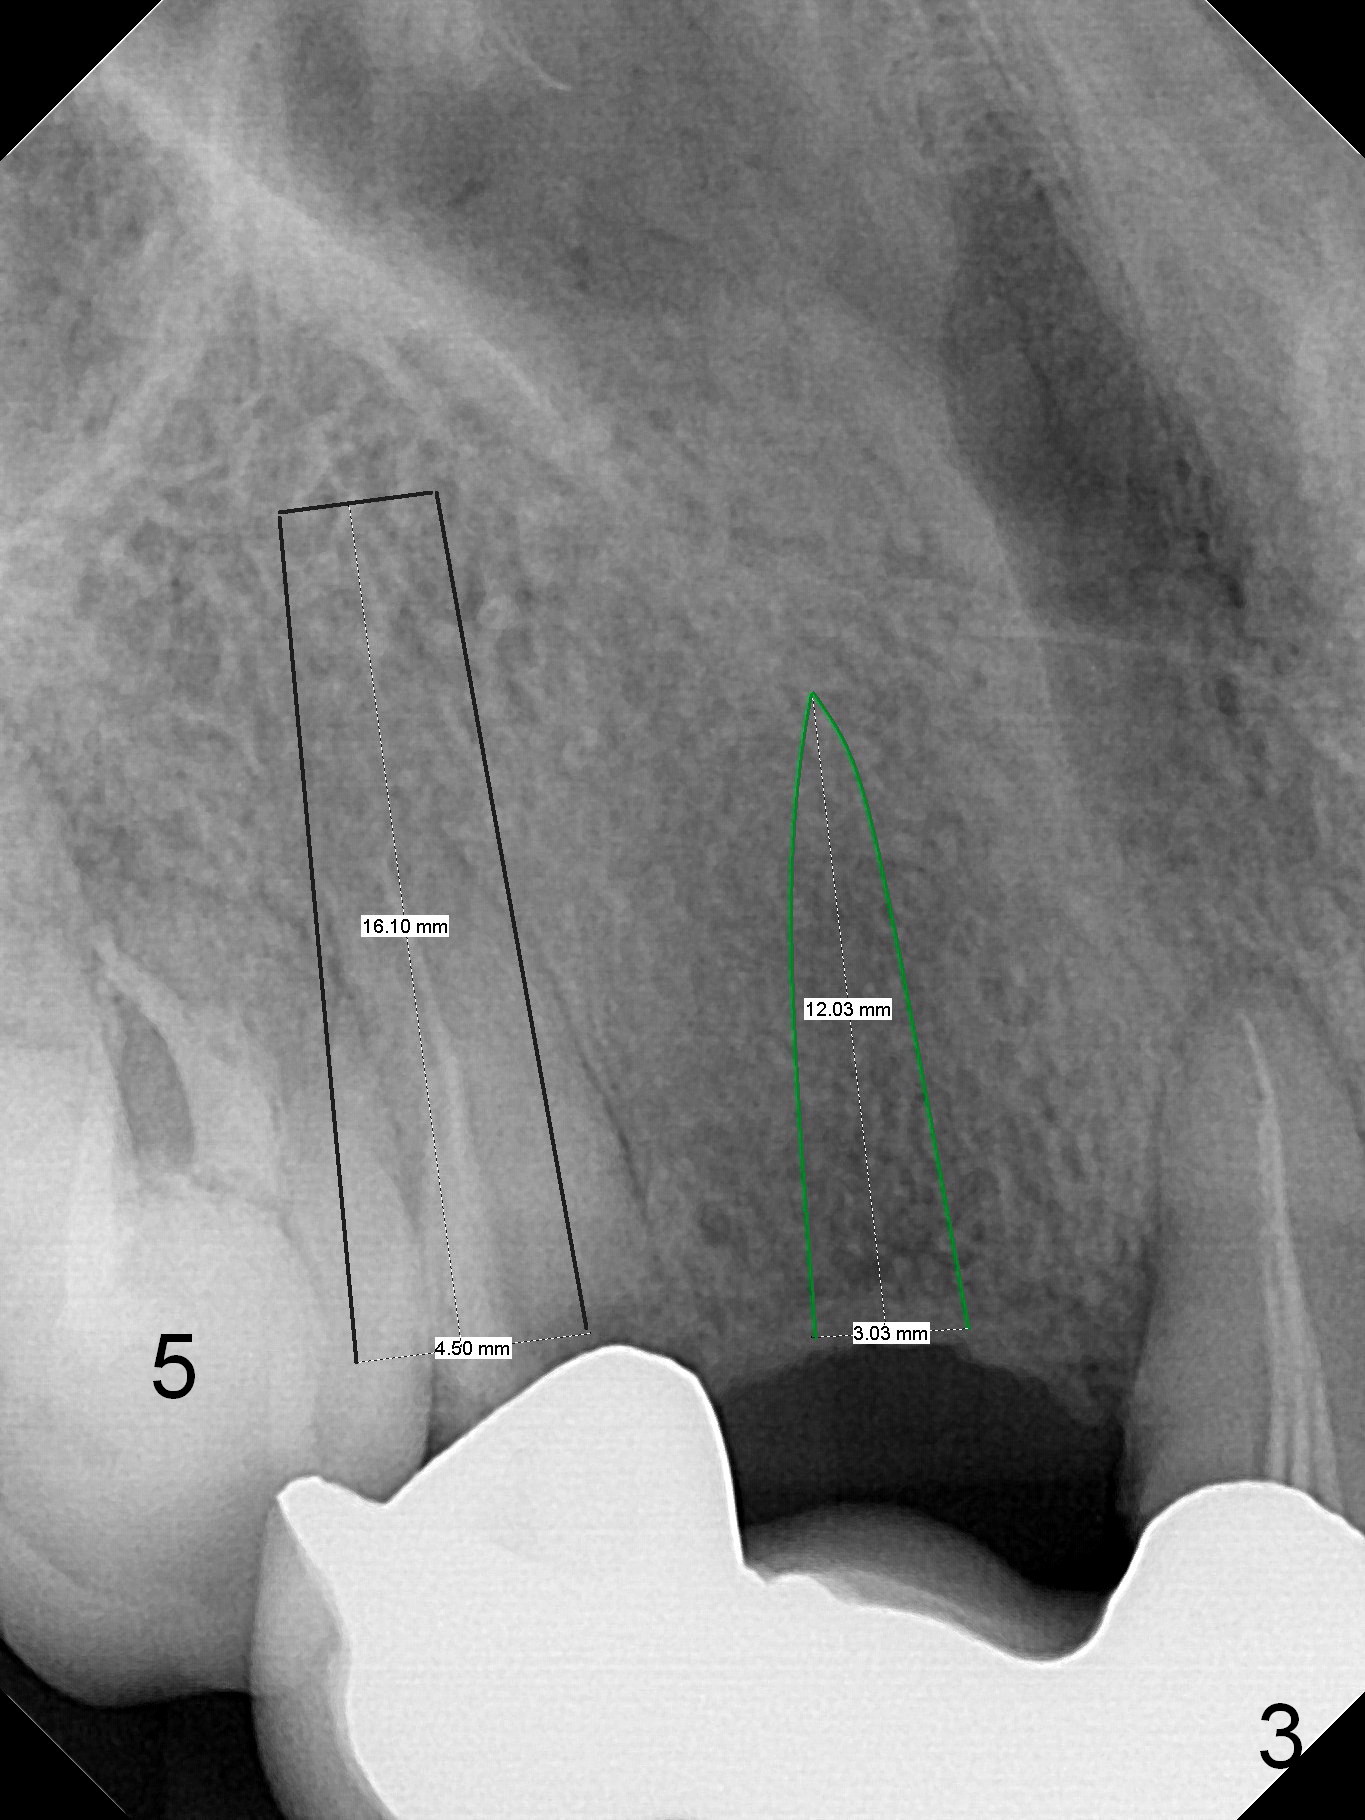

A 43-year-old woman has poor dentition including the tooth #5 (Fig.1) for RCT (Fig.3) and the teeth #2, 30 and 31 are missing. The retainer at #6 fractures (Fig.1 *). After sectioning the bridge between #7 and 8, fabricate prefabricated post at #6 if the latter is salvageable. Otherwise extract (Clindamycin) and implant (Fig.3). Anyway, a 3-mm or smaller one-piece implant is to be placed at #7 for stability and retention. Pay attention to the labial concavity at #7 (Fig.2 *). Surgical stent has been made.